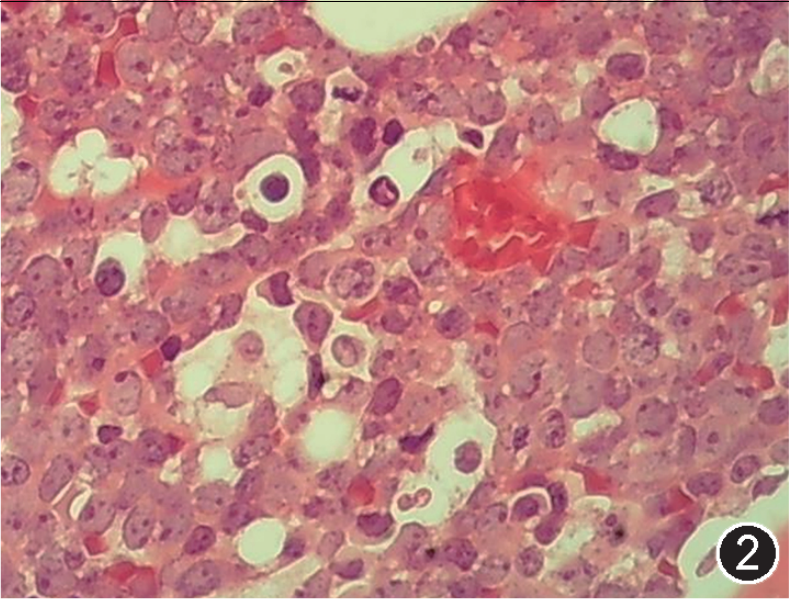

图注:图1 骨髓涂片中的肿瘤细胞(瑞氏染色,×1 000);图2 骨髓活检中的肿瘤细胞(HE, 高倍放大);图3 免疫组织化学染色,CD20部分阳性(EnVision法,中倍放大);图4 免疫组织化学染色,CD19阳性;图5 免疫组织化学染色,CD10阳性;图 6 免疫组织化学染色,MYC阳性,图 7 免疫组织化学染色,bcl-2阴性;图 8 免疫组织化学染色,Ki-67阳性指数约 80%。

该文病例以外周血和骨髓累犯为主要表现,无明显髓外肿块。外周血和骨髓检查发现大量胞体中等至大的原始(母)细胞,形态似ALL。流式细胞学检测示CD5-CD10+B细胞淋巴瘤,不表达原始标记CD34和TdT。

根据以上检查结果,需要考虑的淋巴瘤类型包括BL、HGBL、原始细胞标记阴性B-ALL(占B-ALL<5%)以及罕见CD5-CD10+MCL的母细胞变型,须进一步进行免疫组化(包括CyclinD1、CD10、BCL6、MUM1、MYC、BCL2、Ki67)、染色体核型、FISH检测(MYC、BCL2、BCL6、IgH-CCND1)以及白血病融合基因检测加以区分。最终流式细胞学示肿瘤细胞CD38强表达、表达sIgM、sIgD和胞膜Kappa,免疫组化CyclinD1-,细胞遗传学示复杂核型,FISH检测MYC和bcl-6基因重排阳性,白血病52种融合基因阴性,二代测序提示存在TP53、CCND3、MYC、TCF3、FOXO1等HGBL、DLBCL中而非B-ALL/LBL中的常见基因突变类型,因此综合诊断为HGBL伴MYC和bcl-6基因重排。